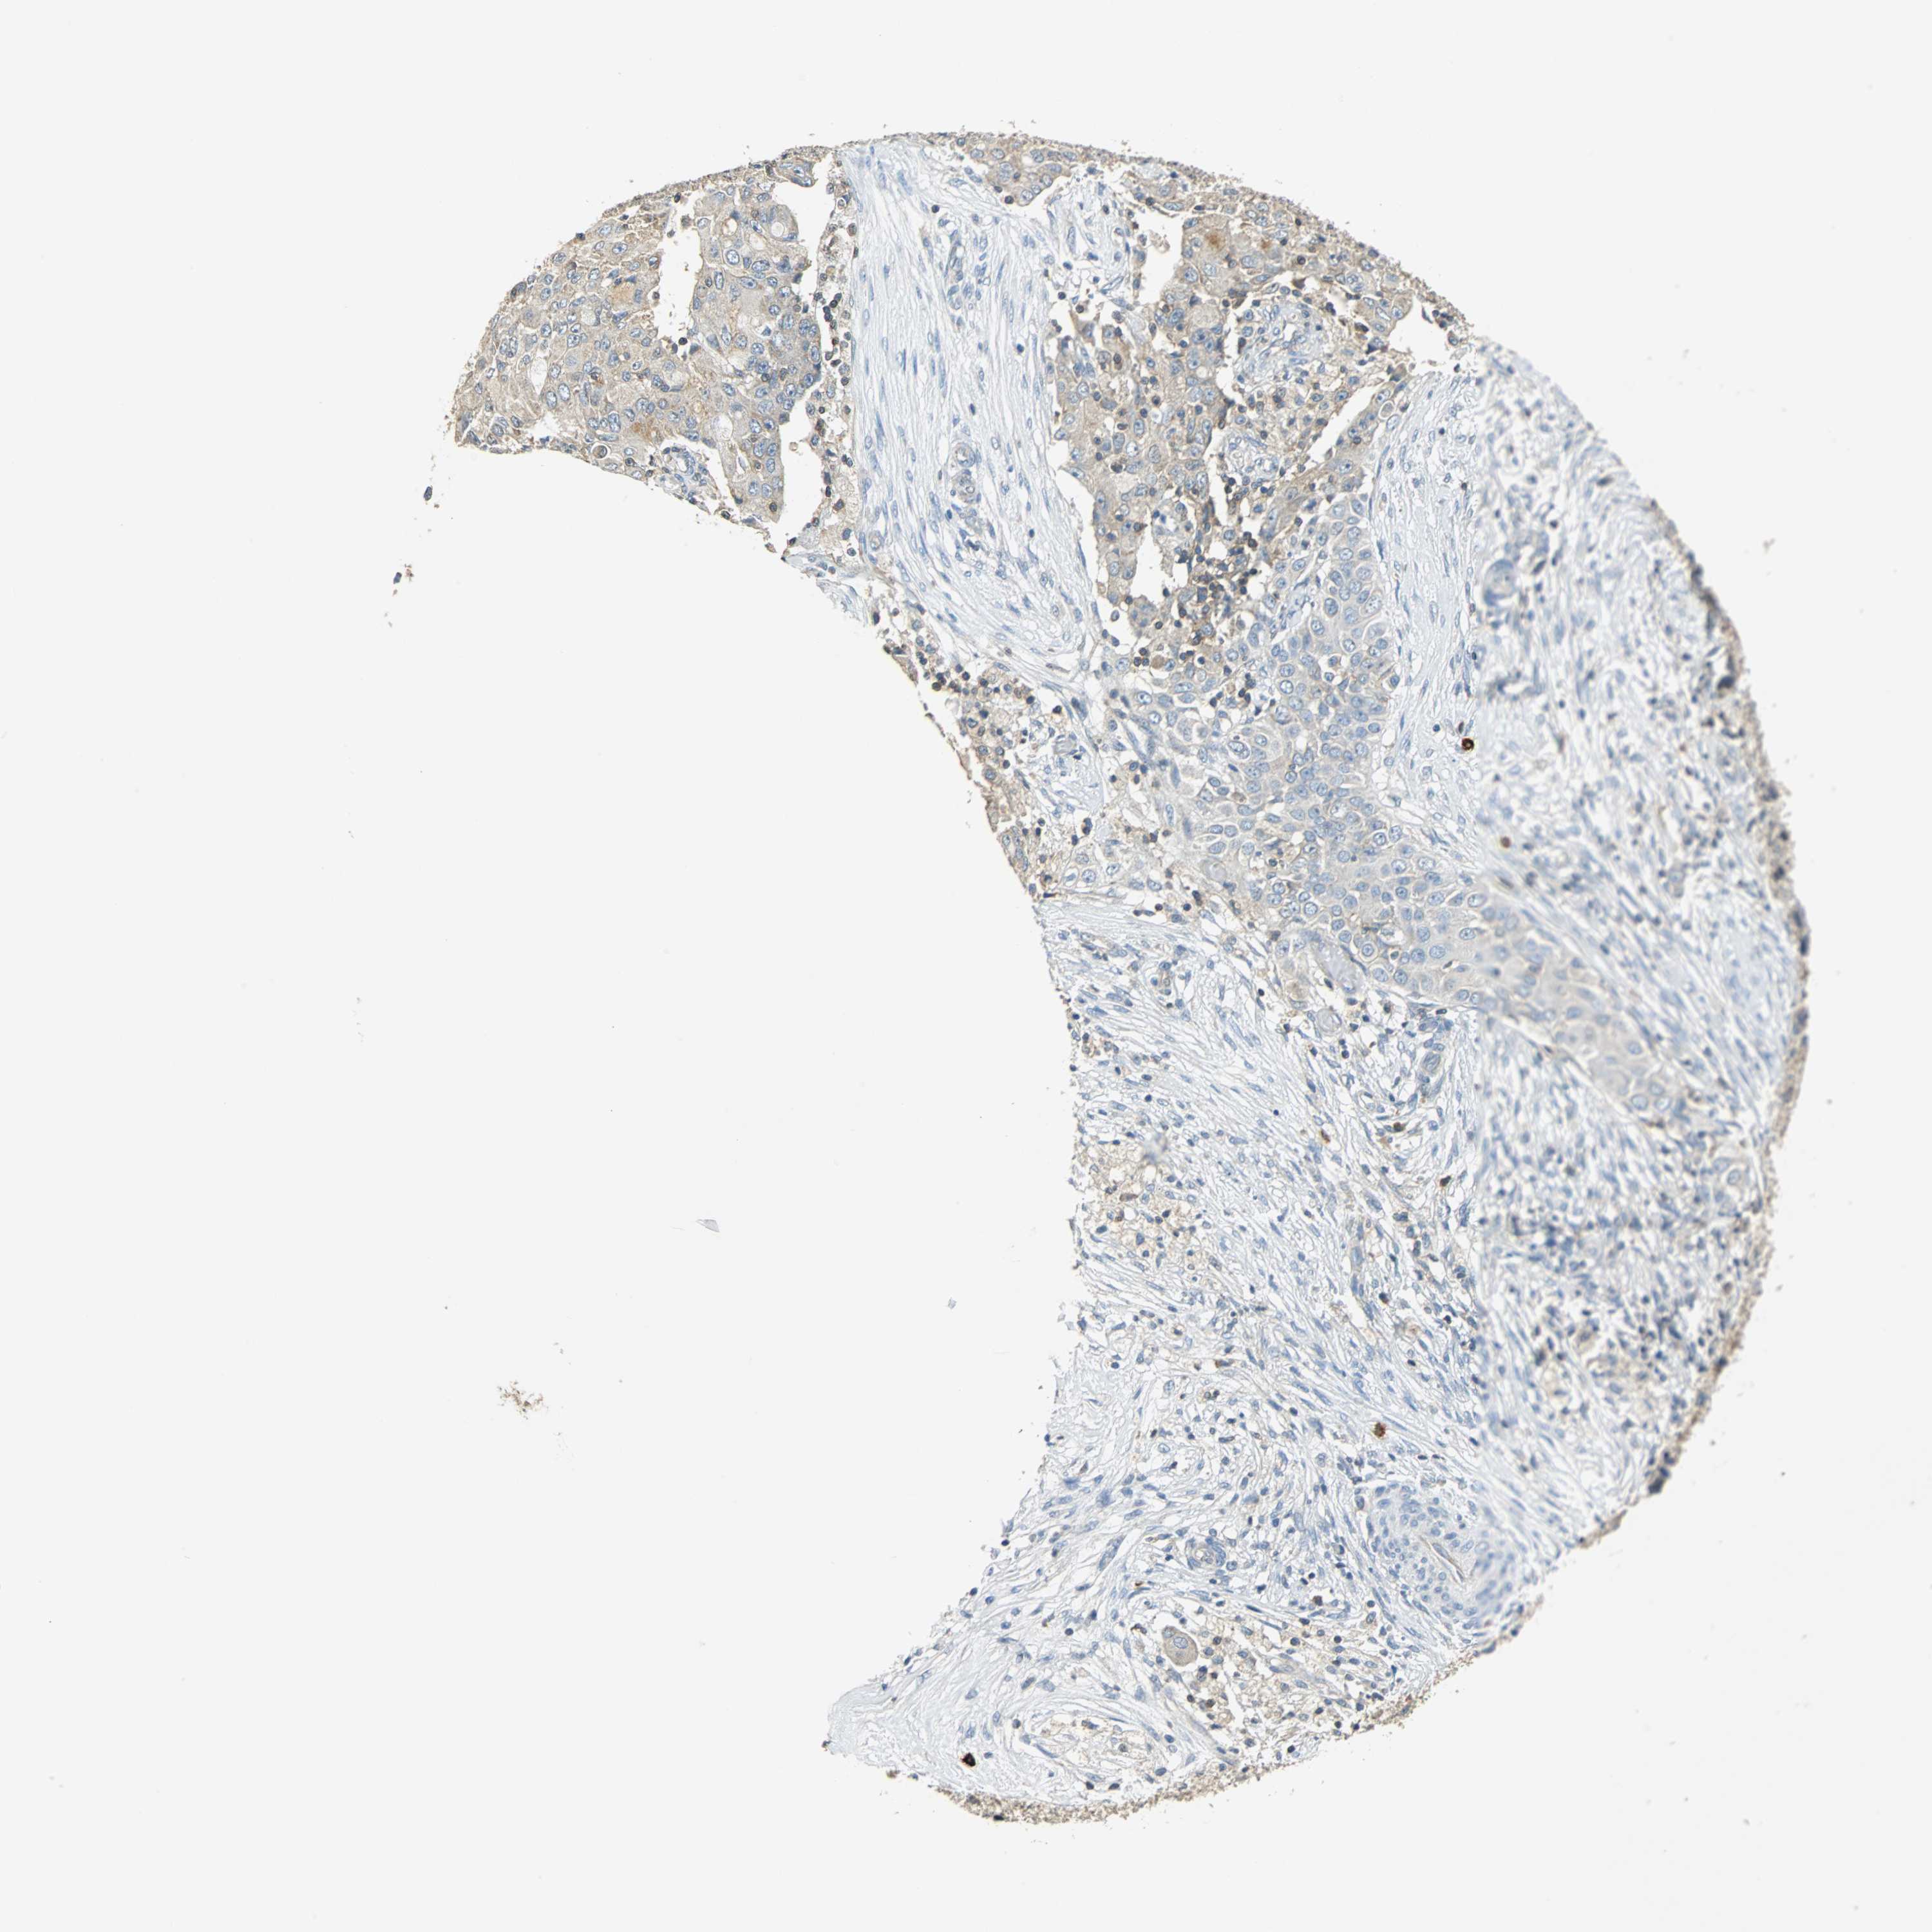

OVARIAN CANCER - Protein expressioni

A mouse-over function shows sample information and annotation data. Click on an image to view it in a full screen mode. Samples can be filtered based on level of antibody staining by selecting one or several of the following categories: high, medium, low and not detected. The assay and annotation is described here.

Note that samples used for immunohistochemistry by the Human Protein Atlas do not correspond to samples in the TCGA dataset.

Antibody stainingi

Antibody staining in the annotated cell types in the current human tissue is reported as not detected, low, medium, or high, based on conventional immunohistochemistry profiling in selected tissues. This score is based on the combination of the staining intensity and fraction of stained cells.

Each image is clickable and will lead to virtual microscopy that enables deeper exploration of all samples and also displays staining intensity scores, fraction scores and subcellular localization as well as patient and tissue information for each sample.

Antibody HPA006479

Antibody HPA008689

Antibody CAB020712

Cystadenocarcinoma, serous, NOS